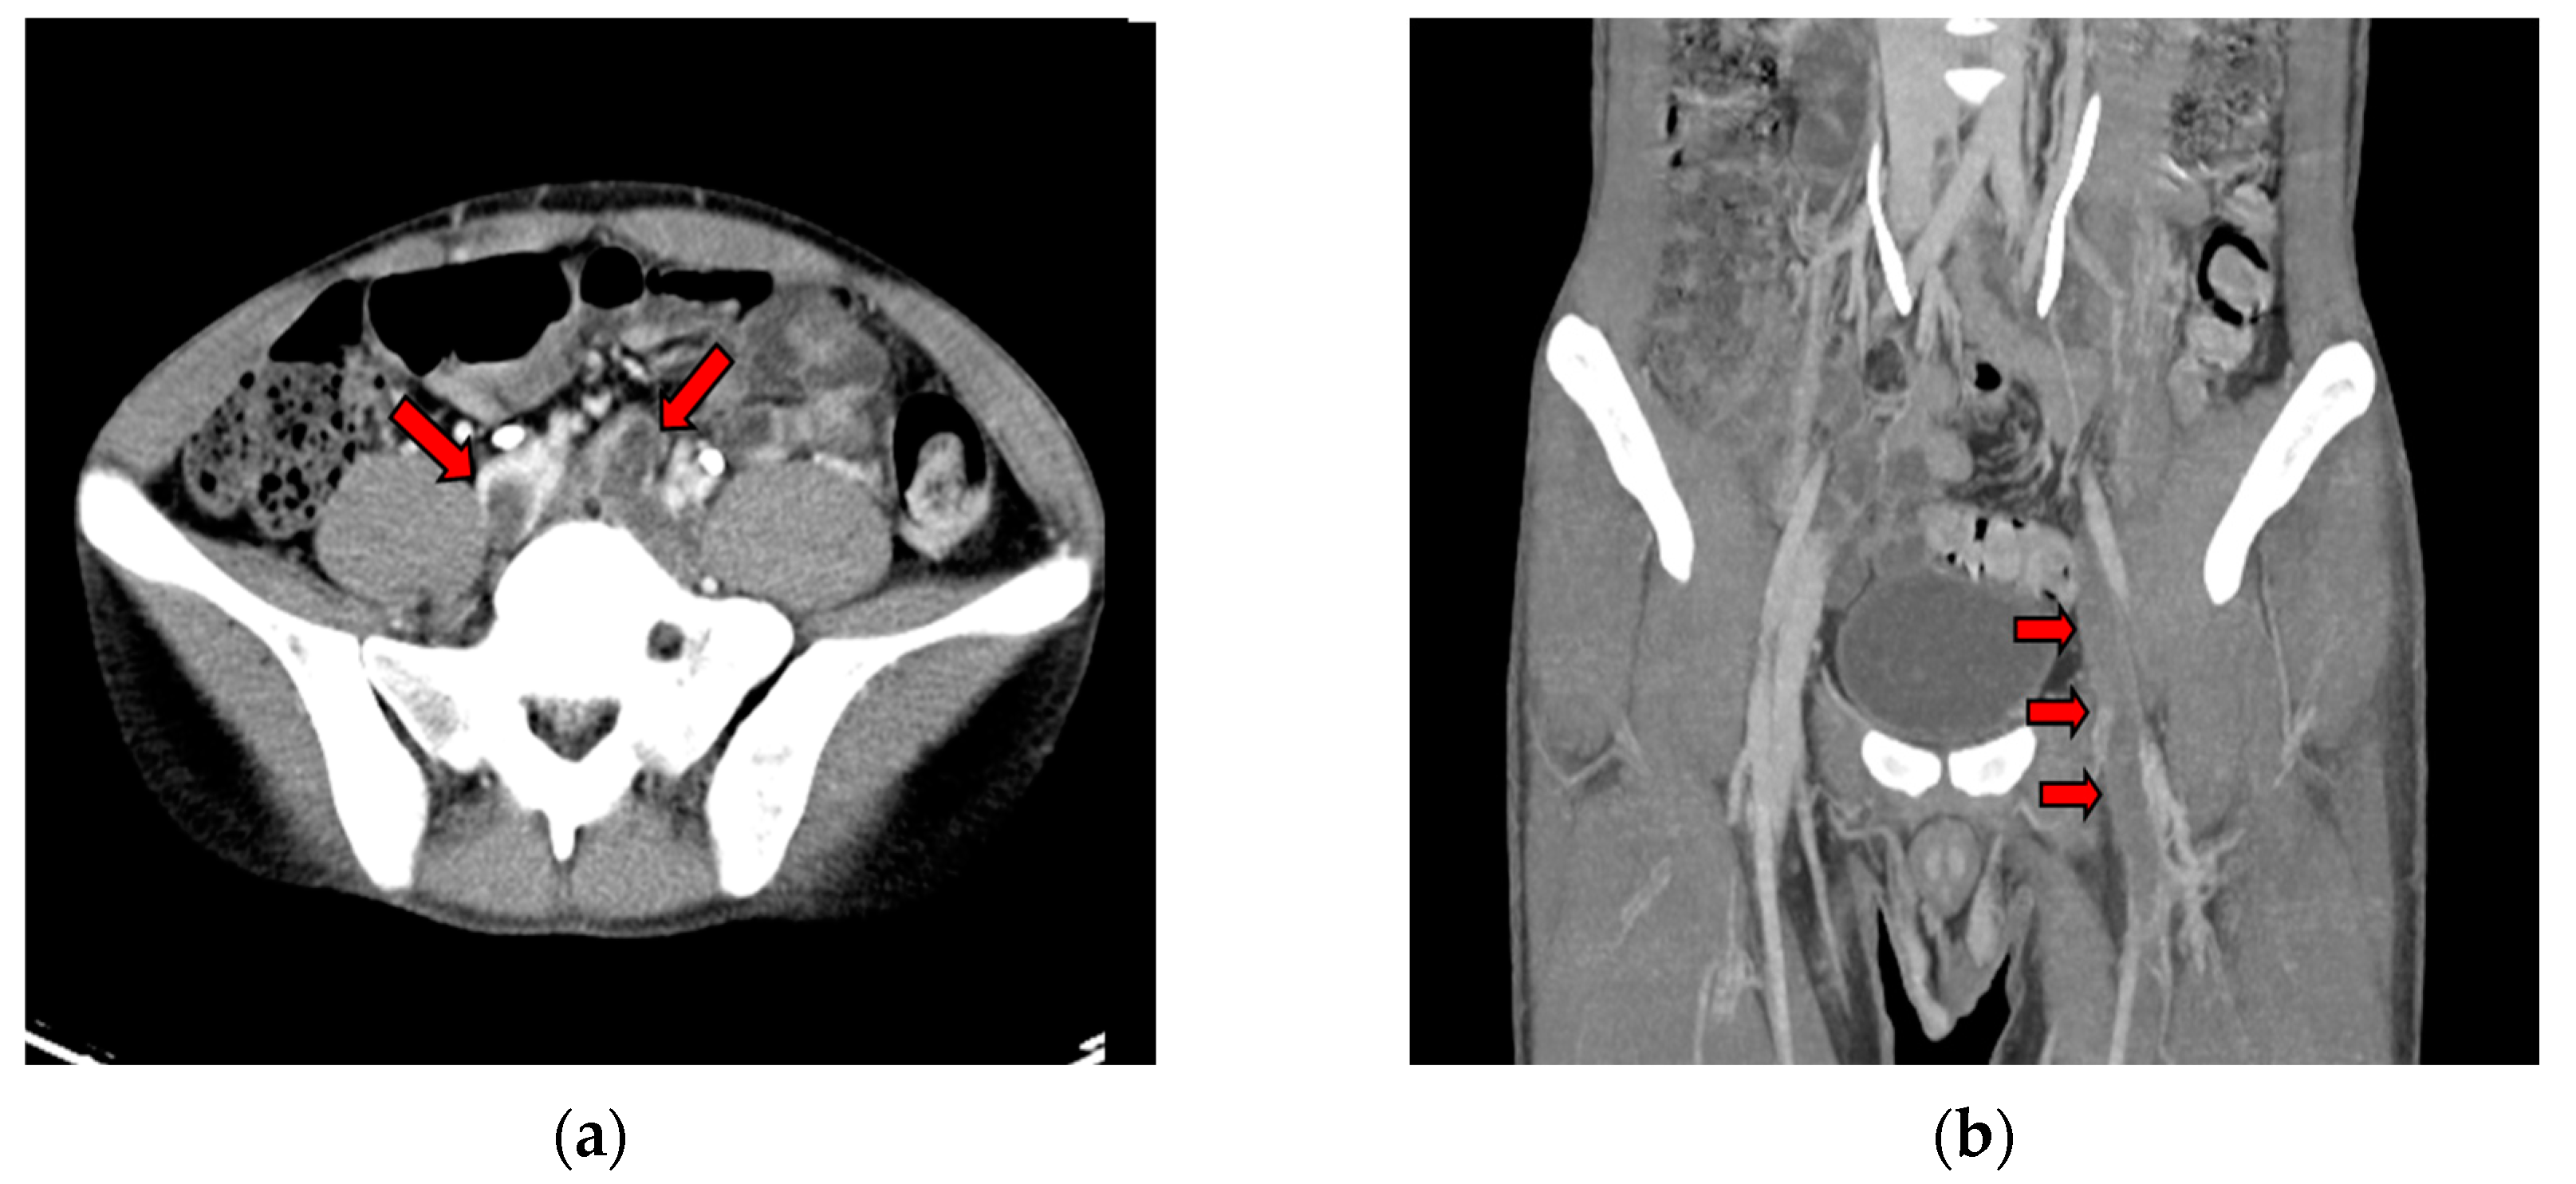

2. Case Report